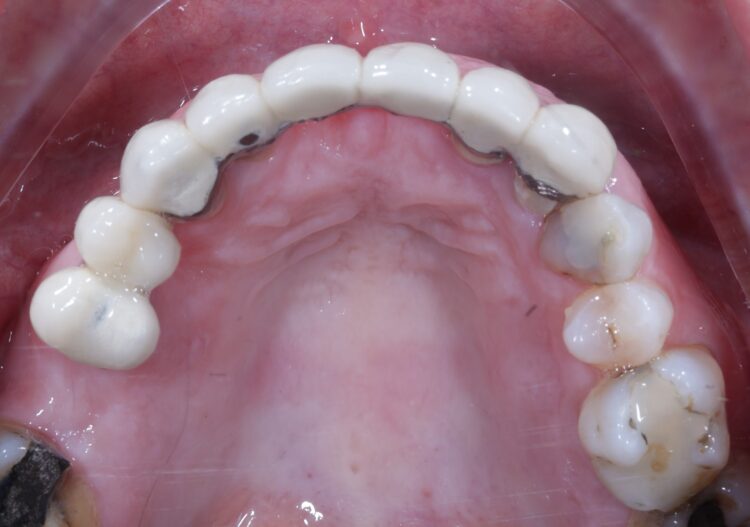

A 61-year-old female patient presented with a failing, upper 3-3, metal ceramic bridge, connected to the canines and lateral incisors on either side. The bridge had failed with caries and core fractures on both abutment teeth on the patient’s left side. As such, the patient was keen to repair or replace the bridge without the use of a removable prosthesis at any point during treatment.

On the day of surgery, the first step was to carefully dismantle the bridge while avoiding any damage to the teeth we wanted to keep on the right-hand side. The prosthesis was sectioned and removed in several pieces.

Non-engaging cylinders were placed onto the implants to connect to the pre-fabricated temporary bridge. A premade temporary bridge was connected, contoured and polished, with particular attention paid to the contour of the restoration and suturing with the aim of prosthetically guided soft tissue healing.

The patient returned to the practice for review two weeks post-surgery and to confirm successful and otherwise uneventful healing. Discomfort was minimal and she reported being very satisfied with the outcome. After a healing period of three months, the patient returned to begin making the final prosthesis. Good soft tissue adaptation was noted around the temporary prosthesis and the buccal contour was successfully maintained.